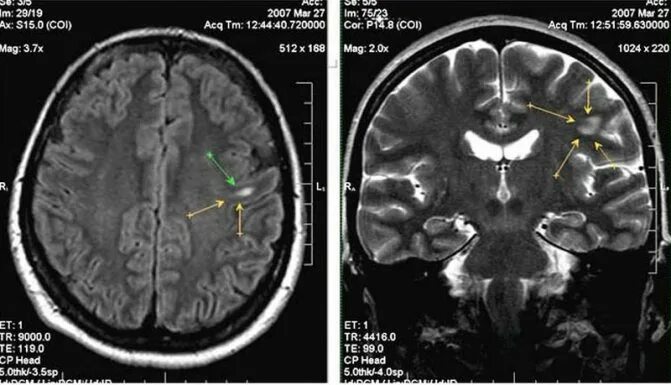

Белые очаги в головном мозге